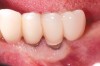

Dental implants have revolutionized the way in which clinicians treat and restore partially and fully edentulous patients and have demonstrated success for managing a broad range of clinical dilemmas. While implants have been highly predictable and have achieved long-term success, they are not immune from complications associated with improper treatment planning, poor surgical and prosthetic execution, material failure, and inadequate or infrequent maintenance. Among these problems are the biologic complications of peri-implant mucositis and peri-implantitis, which are inflammatory conditions in the soft and/or hard tissues surrounding dental implants (Figure 1 through Figure 4).1,2

Fig 1. Clinical view of severe gingival inflammation with possible early bone loss present around the implant at the site of the maxillary left first molar. The two premolar implants had mucogingival deformities.

Figure 1